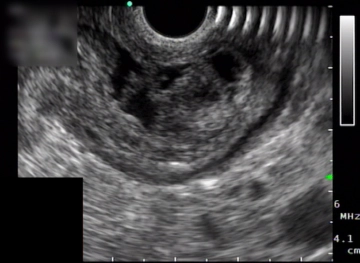

Configurações de som A operação começa com uma exploração laparoscópica do abdômen para excluir metástases peritoneais e hepáticas. No decorrer disso, uma colecistectomia oportunista é realizada independentemente da operação do tumor (não mostrado). Após a fenestração do ligamento gastrocolico com abertura da bolsa omental, a parede posterior do estômago torna-se visível. O tumor pré-pilórico parece ser bem ressecável. Endossonograficamente, este tumor corresponde a uma massa eco-heterogênea de 26 × 12 mm dentro da parede gástrica.